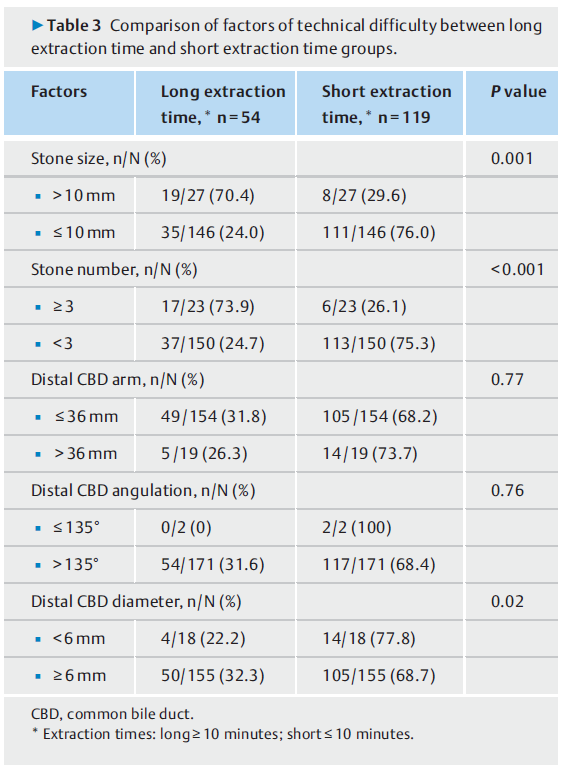

需要较长的取石时间才能去除困难结石,如(表3)所示,在较长的取石时间组中检测到较大和多个结石的频率较高。

表3. 长提取时间组和短提取时间组技术难度因素的比较